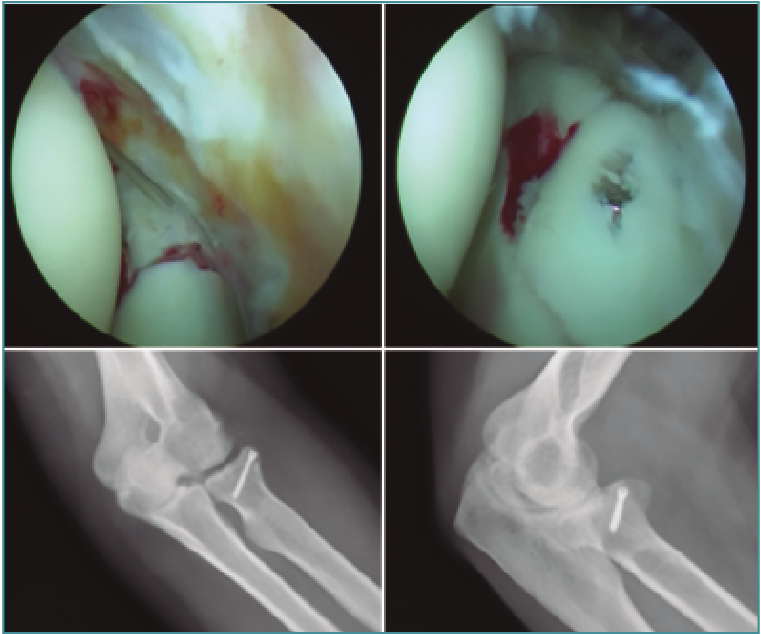

La reducción abierta y la fijación interna es el tratamiento recomendado para las fracturas de tipo III debido a la alta incidencia de inestabilidad asociada con estos grandes fragmentos de fractura. La intervención quirúrgica también se recomienda para cualquier fractura del proceso coronoide que interfiera con el movimiento articular(4). Si hay un alto grado de conminución de la fractura coronoide y no es posible la fijación interna, se indica la colocación de fijación externa para mantener la congruencia de la articulación del codo durante la cicatrización del tejido blando y óseo. Cuando hay presente un gran fragmento de fractura de un proceso coroideo, sin embargo, puede visualizarse y asegurarse de forma efectiva utilizando técnicas artroscópicas. Se puede fijar con AK o bien insertar una guía de ligamento cruzado anterior tibial a través del portal medial anterior y se usa para manipular y reducir anatómicamente el fragmento de la fractura. A continuación, taladramos el olécranon desde fuera hacia la articulación controlado con visión directa hasta atravesar la fractura de la coronoides. Luego, se puede usar distintas técnicas, desde una lazada con sutura de alta resistencia (Figura 7) hasta un pequeño tornillo canulado para asegurar el fragmento de fractura del proceso coronoide y ayudar a restablecer la estabilidad de la articulación(5).

Figura 7. Fractura de coronoides asistida por artroscopia con sistema de lazada.

Las fracturas de cabeza radial desplazadas en 2 partes a menudo son susceptibles de evaluación y tratamiento artroscópico. La mayoría de los autores creen que, si el fragmento desplazado bloquea la rotación del antebrazo, está indicada la intervención quirúrgica. La visualización a través del portal medial anterior proximal permite evaluar no solo la incongruencia articular, sino también la estabilidad del fragmento de fractura a través de un rango de rotación del antebrazo(7). Cualquier bloqueo óseo a la rotación también se identifica fácilmente. Tras lavar la articulación del codo con suero y desbridar los coágulos, se aprecia de forma clara el tipo de fractura y el número de fragmentos óseos. A continuación, se puede utilizar una AK de 1,8-2,2 mm a modo de joystick para permitir la manipulación y reducción de algunas fracturas de cabeza radial de 2 partes. Después de la reducción se puede utilizar un tornillo canulado de tipo Herbert o similar para asegurar la fijación (Figura 8). Para este procedimiento, es obligatorio conocer a fondo la anatomía neurovascular y la ubicación del portal. Los tornillos pueden colocarse percutáneamente a través de los portales establecidos o nuevas incisiones exclusivas para introducirlos en la dirección óptima. Cada fractura es diferente y puede requerir diferentes ángulos de inserción del tornillo. Este tornillo autocomprimible proporciona buena estabilidad y permite un movimiento temprano. Este implante también se puede enterrar completamente debajo del borde articular del cartílago de la cabeza radial, evitando así la obstrucción del dispositivo en la articulación radiocubital proximal.

Figura 8. Fractura de la cabeza radial asistida por artroscopia.